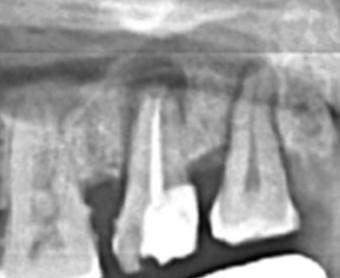

Male patient . Age:-  62 years. Well controlled diabetes and hypertension. Tooth : 2-7 /  Upper right second molar

2-7 / UR second molar was badly infected and was extracted on  16/04/2021 . As can be seen on the OPG the wound is not completely healed ( or at least the bony healing has yet to occur ). Should I attempt implant placement in 2-7 / Upper right second molar.

If yes , what should be the procedure and precautions to be take. I use Osstem implants.

Hope to see a lot of responses and many thanks in advance for the same. Please find below the latest OPG as well as the OPG before extraction.